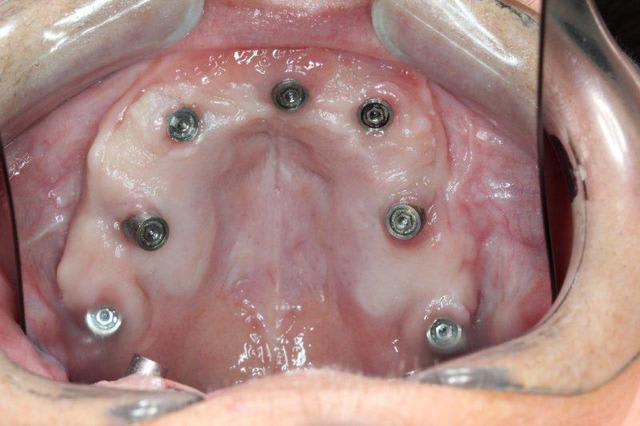

Je vais te filer qques photos d une patiente opérée voici 3 ans avec du nano et des plaques rien que l aspect de la muqueuse te montrera que tout ça est sain et ossifié

Par contre je peux te dire que les 4 plaques et même le monodisk sont sonores et parfaitement indolores donc a priori intégrés béton

Alors deux petites photos pour vous dire que je vais bien

Pour posit, les cylindres ont tous été posés à main levée et je pense que c est pas si mal que ça ;-)